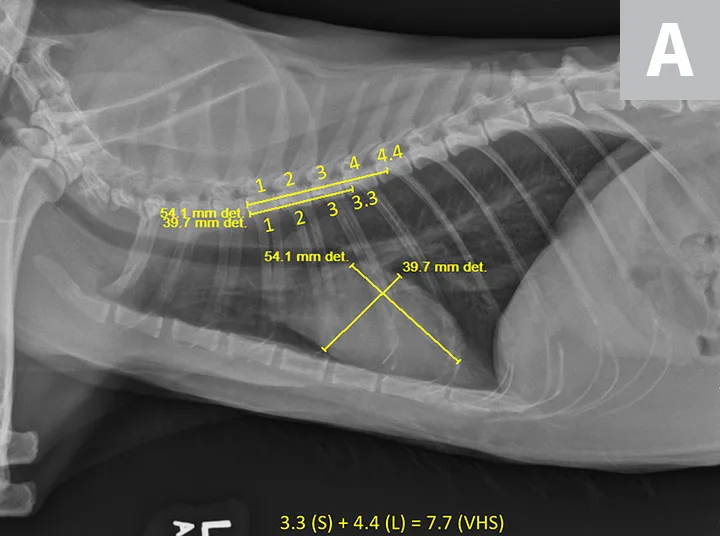

VHS calculation in a clinically normal cat using a left lateral radiograph (A). L (ie, long axis; 4.4) is drawn from the carina to the most ventral aspect of the apex. S (ie, short axis; 3.3) is drawn perpendicular to L at the widest aspect of the heart, extending to the cranial and caudal borders. S and L are transposed along the spine from the cranial aspect of T4 using calipers. The number of vertebrae traversed (rounded to the nearest tenth) are summed to calculate VHS (7.7). Orthogonal radiograph of the patient is also shown for more complete evaluation of cardiac silhouette (B).

Thoracic radiographs revealed a normal-sized cardiac silhouette with VHS 7.7 and no signs of CHF (Figure 1), as well as a redundant aorta caused by exaggerated horizontal positioning of the cardiac silhouette that increased the prominence of the aortic arch, a real and common age-related change considered normal in older cats.25 Remaining thoracic structures were unremarkable. Although heart disease could not be ruled out without echocardiography, there was no evidence of structural changes causing cardiac enlargement.